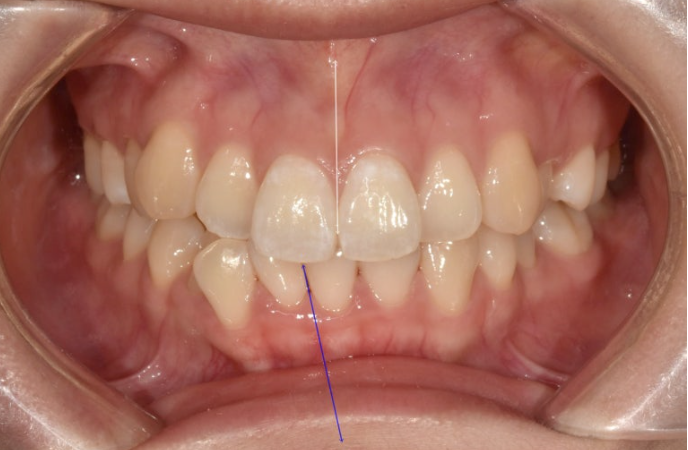

중심선이 약 3mm 어긋나 있습니다.

덧니가 보이고 파란화살표에 소구치에 가위교합도 있습니다.